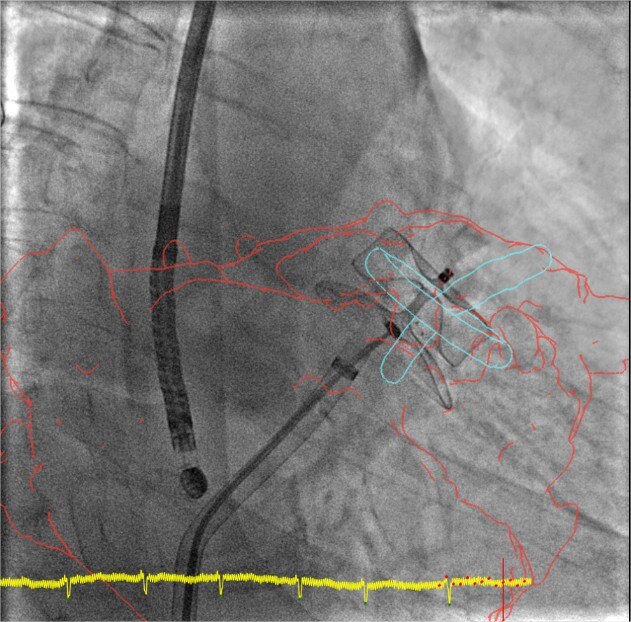

product-product-categories-Intervantional - 2016-valve_22.jpgКонтроль

Функция совмещения трехмерных изображений позволяет контролировать каждый этап, начиная с транссептальной пункции и заканчивая разверткой устройства. Существенно сокращает время процедуры, а также количество используемого контрастного вещества.